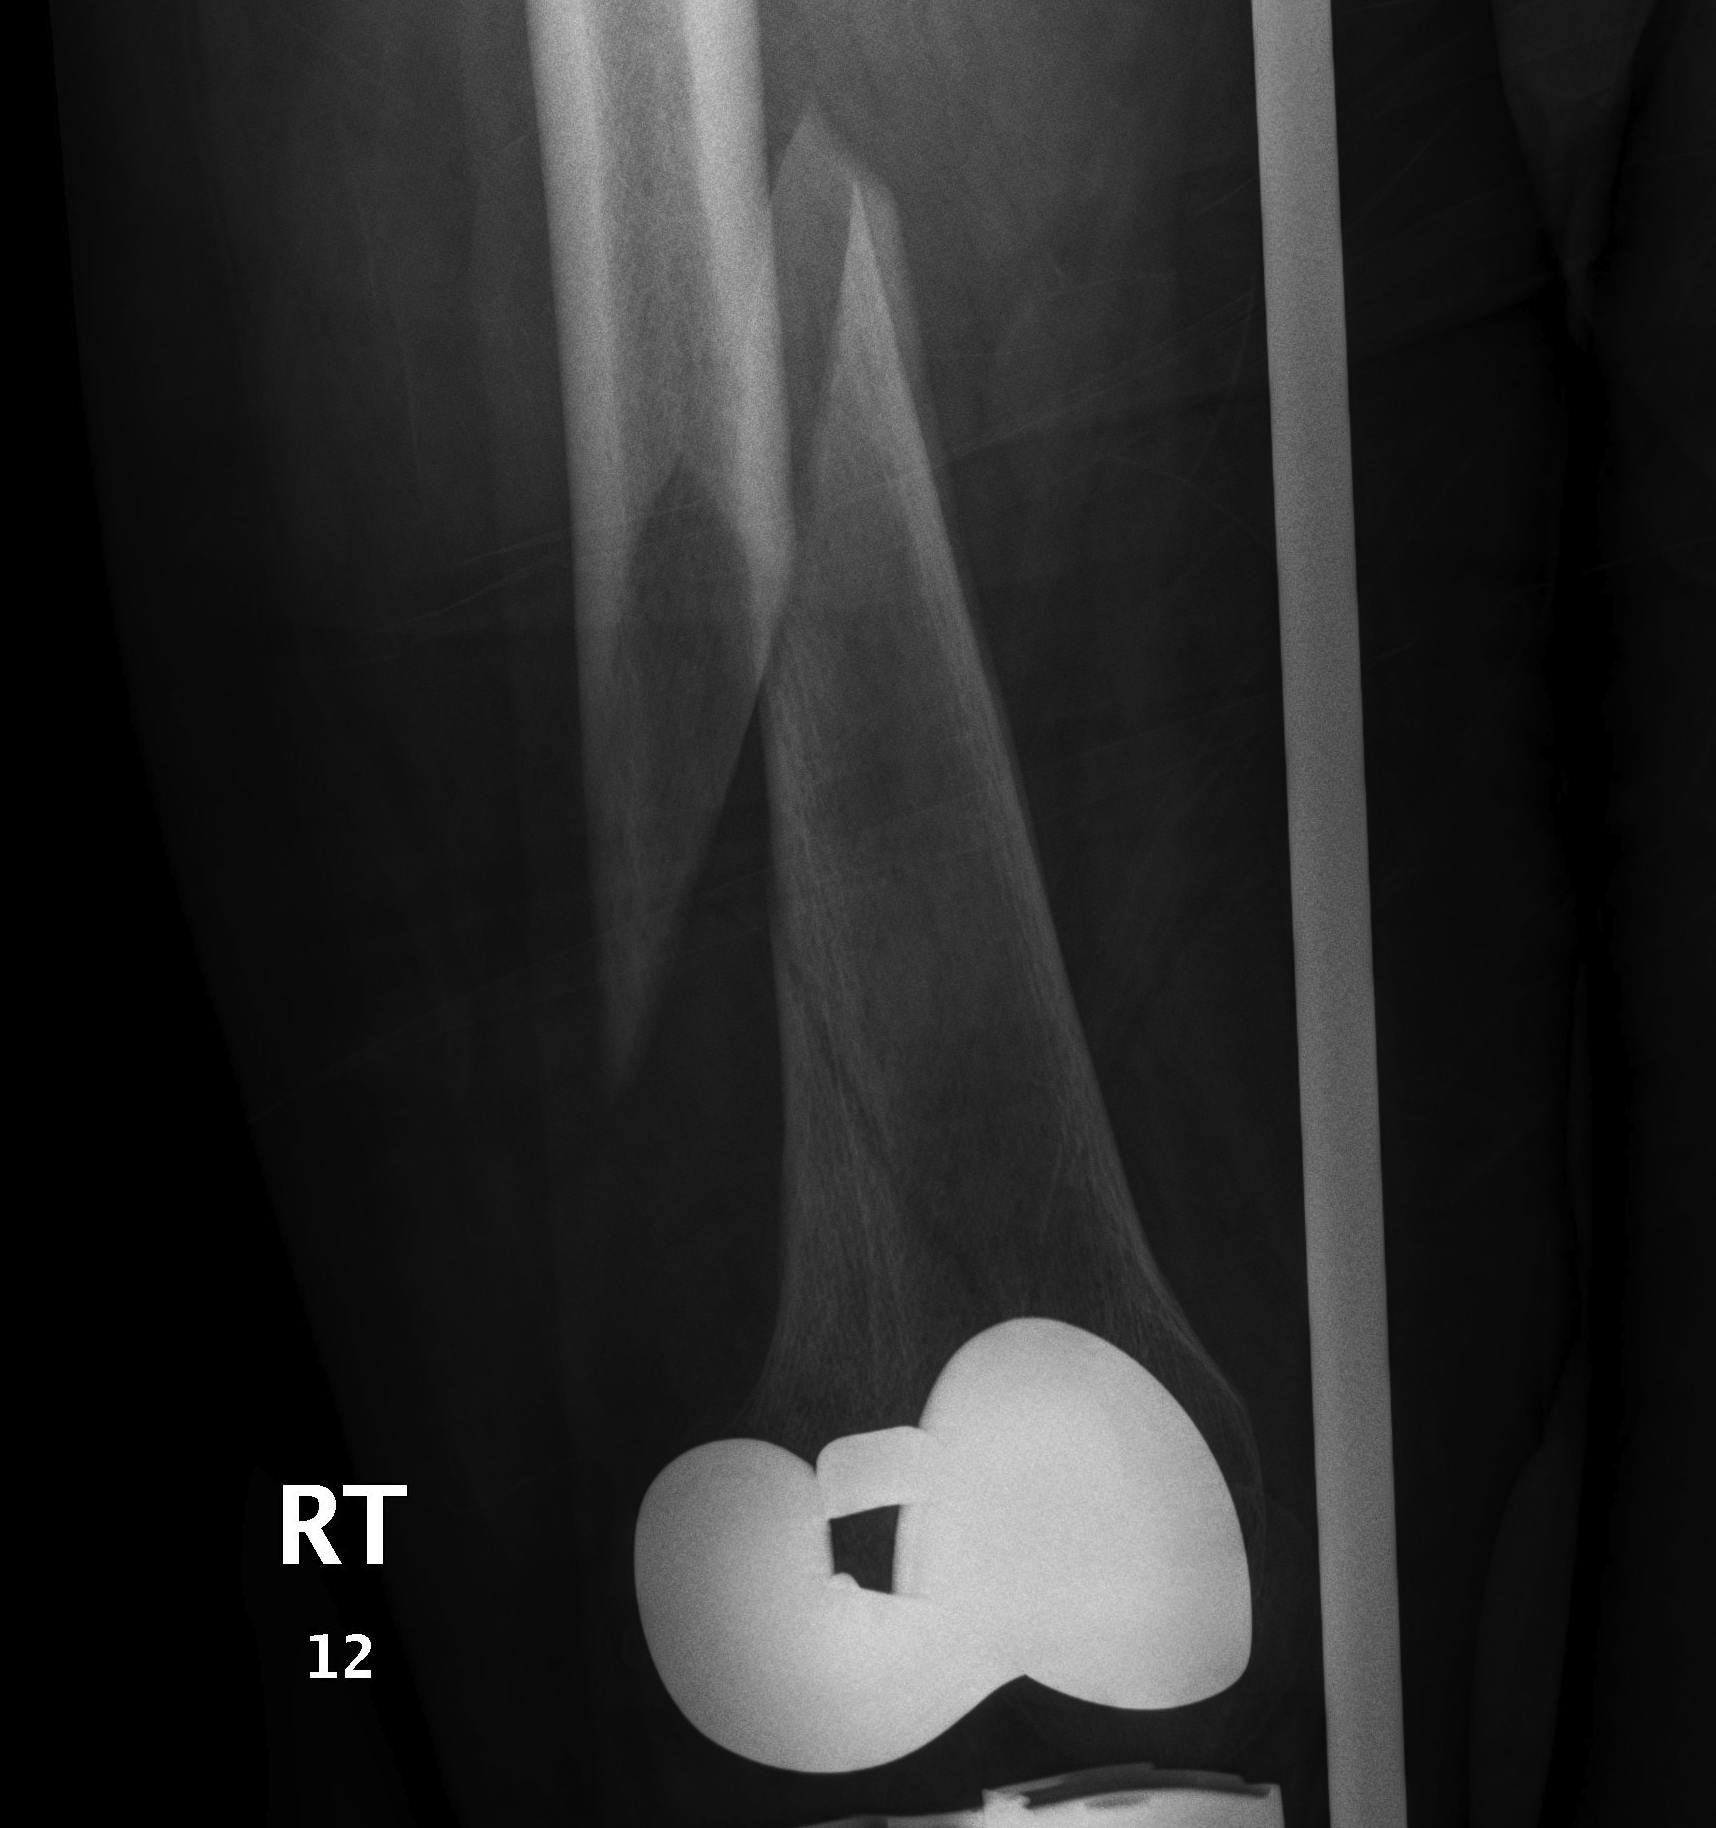

2.  Retrograde IM Nail

TKR Periprosthetic FractureTKR Periprosthetic Fracture 2TKR Periprosthetic Fracture Retrograde Nail 1TKR Periprosthetic Fracture Retrograde Nail 2

Issue

May be biomechanically superior

Have to open TKR to perform operation

Indications

Technically feasible

- CR knees contra-indicated

- must have sufficient sized hole in PS femoral component

- consult company as to suitablity

- small diameter nail

Technique

Minimum intercondylar distance of 12 mm

- AGC 18MM

- PFC = 20MM

- Genesis = 20MM

Usually remove polyethylene component

- replace after nail

- usually need new poly